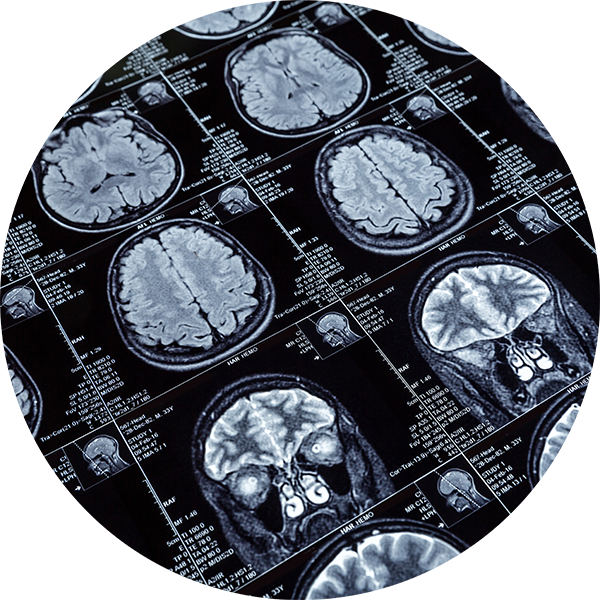

MSA is a rare, rapidly progressing neurodegenerative disorder that affects the brain. MSA impairs the systems that regulate blood pressure, heart rate and the bladder – many of the basic bodily functions that people take for granted every day.